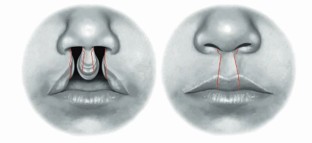

Manchester W M. The repair of bilateral cleft lip and palate. Br J Surg 1965; 52: 878-882.

Millard D R Jr. Closure of bilateral cleft lip and elongation of columella by two operations in infancy. Plast Reconstr Surg 1971; 47: 324-331.

Mulliken J B. Repair of bilateral complete cleft lip and nasal deformity-state of the art. Cleft Palate Craniofac J 2000; 37: 342-347.